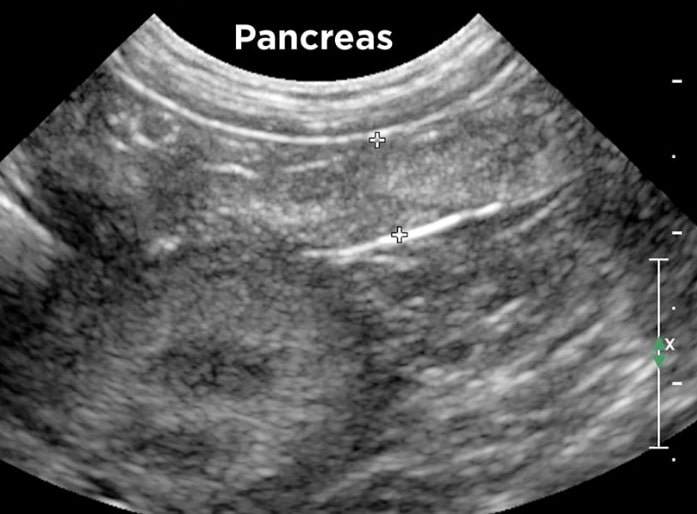

- Abdominal ultrasound to visualize inflammation